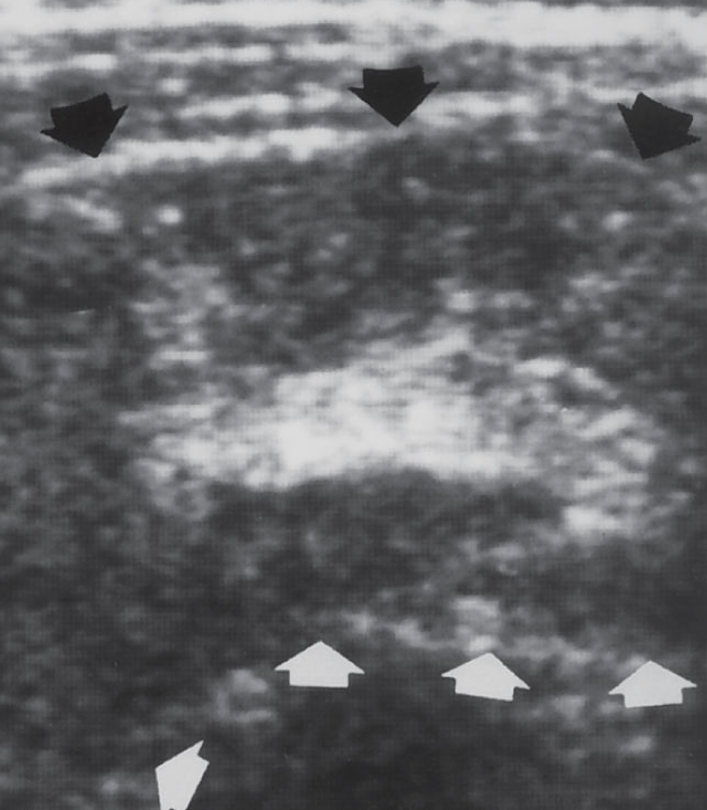

what is shown?

target or donut sign associated with intussusception